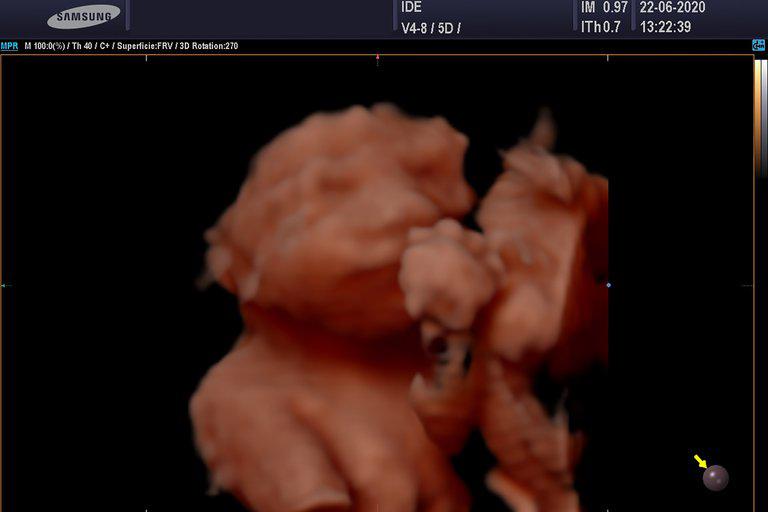

Una ecografía 5D con fecha del 22 de junio. "A medida que van creciendo, se ve cómo las trigemelas interactúan: cuando le querés enfocar la cara a una, la otra se le tapa con un pie. Es muy divertido”, dice la ecografista

Por su parte, María Inés Visco agrega: “Yo sigo maravillada. Las nenas tienen exactamente la misma porción de placenta cada una. A medida que van creciendo, se ve cómo interactúan: cuando le querés enfocar la cara a una, la otra se le tapa con un pie. Es muy divertido”.